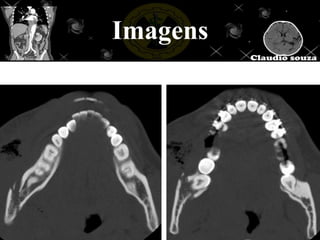

Imagens